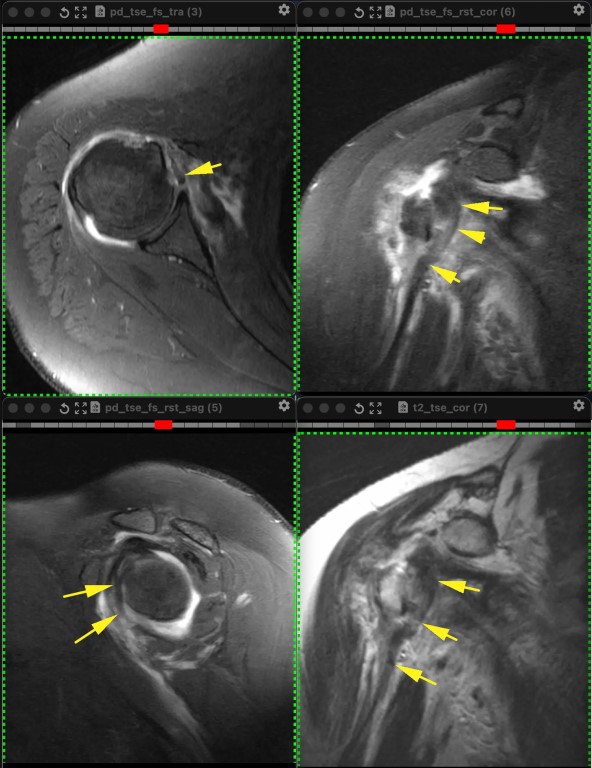

Фото Из-за отрыва сухожилия подлопаточной мышцы вывихнулось медиально сухожилие длинной головки бицепса. Сухожилие подлопаточной мышцы является одновременно удерживателем длинной головки бицепса в межбугорковой борозде, вплетаясь в малый бугорок плеча и как бы продолжаясь в поперечную связку (связку Броди), которую некоторые считают не истинной связкой, а частью сухожилия надостной мышцы.